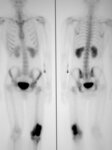

Bone scan; high radionuclide uptake at tumor site

Personal collections of Dr Michael J. Klein and Dr Luminita Rezeanu